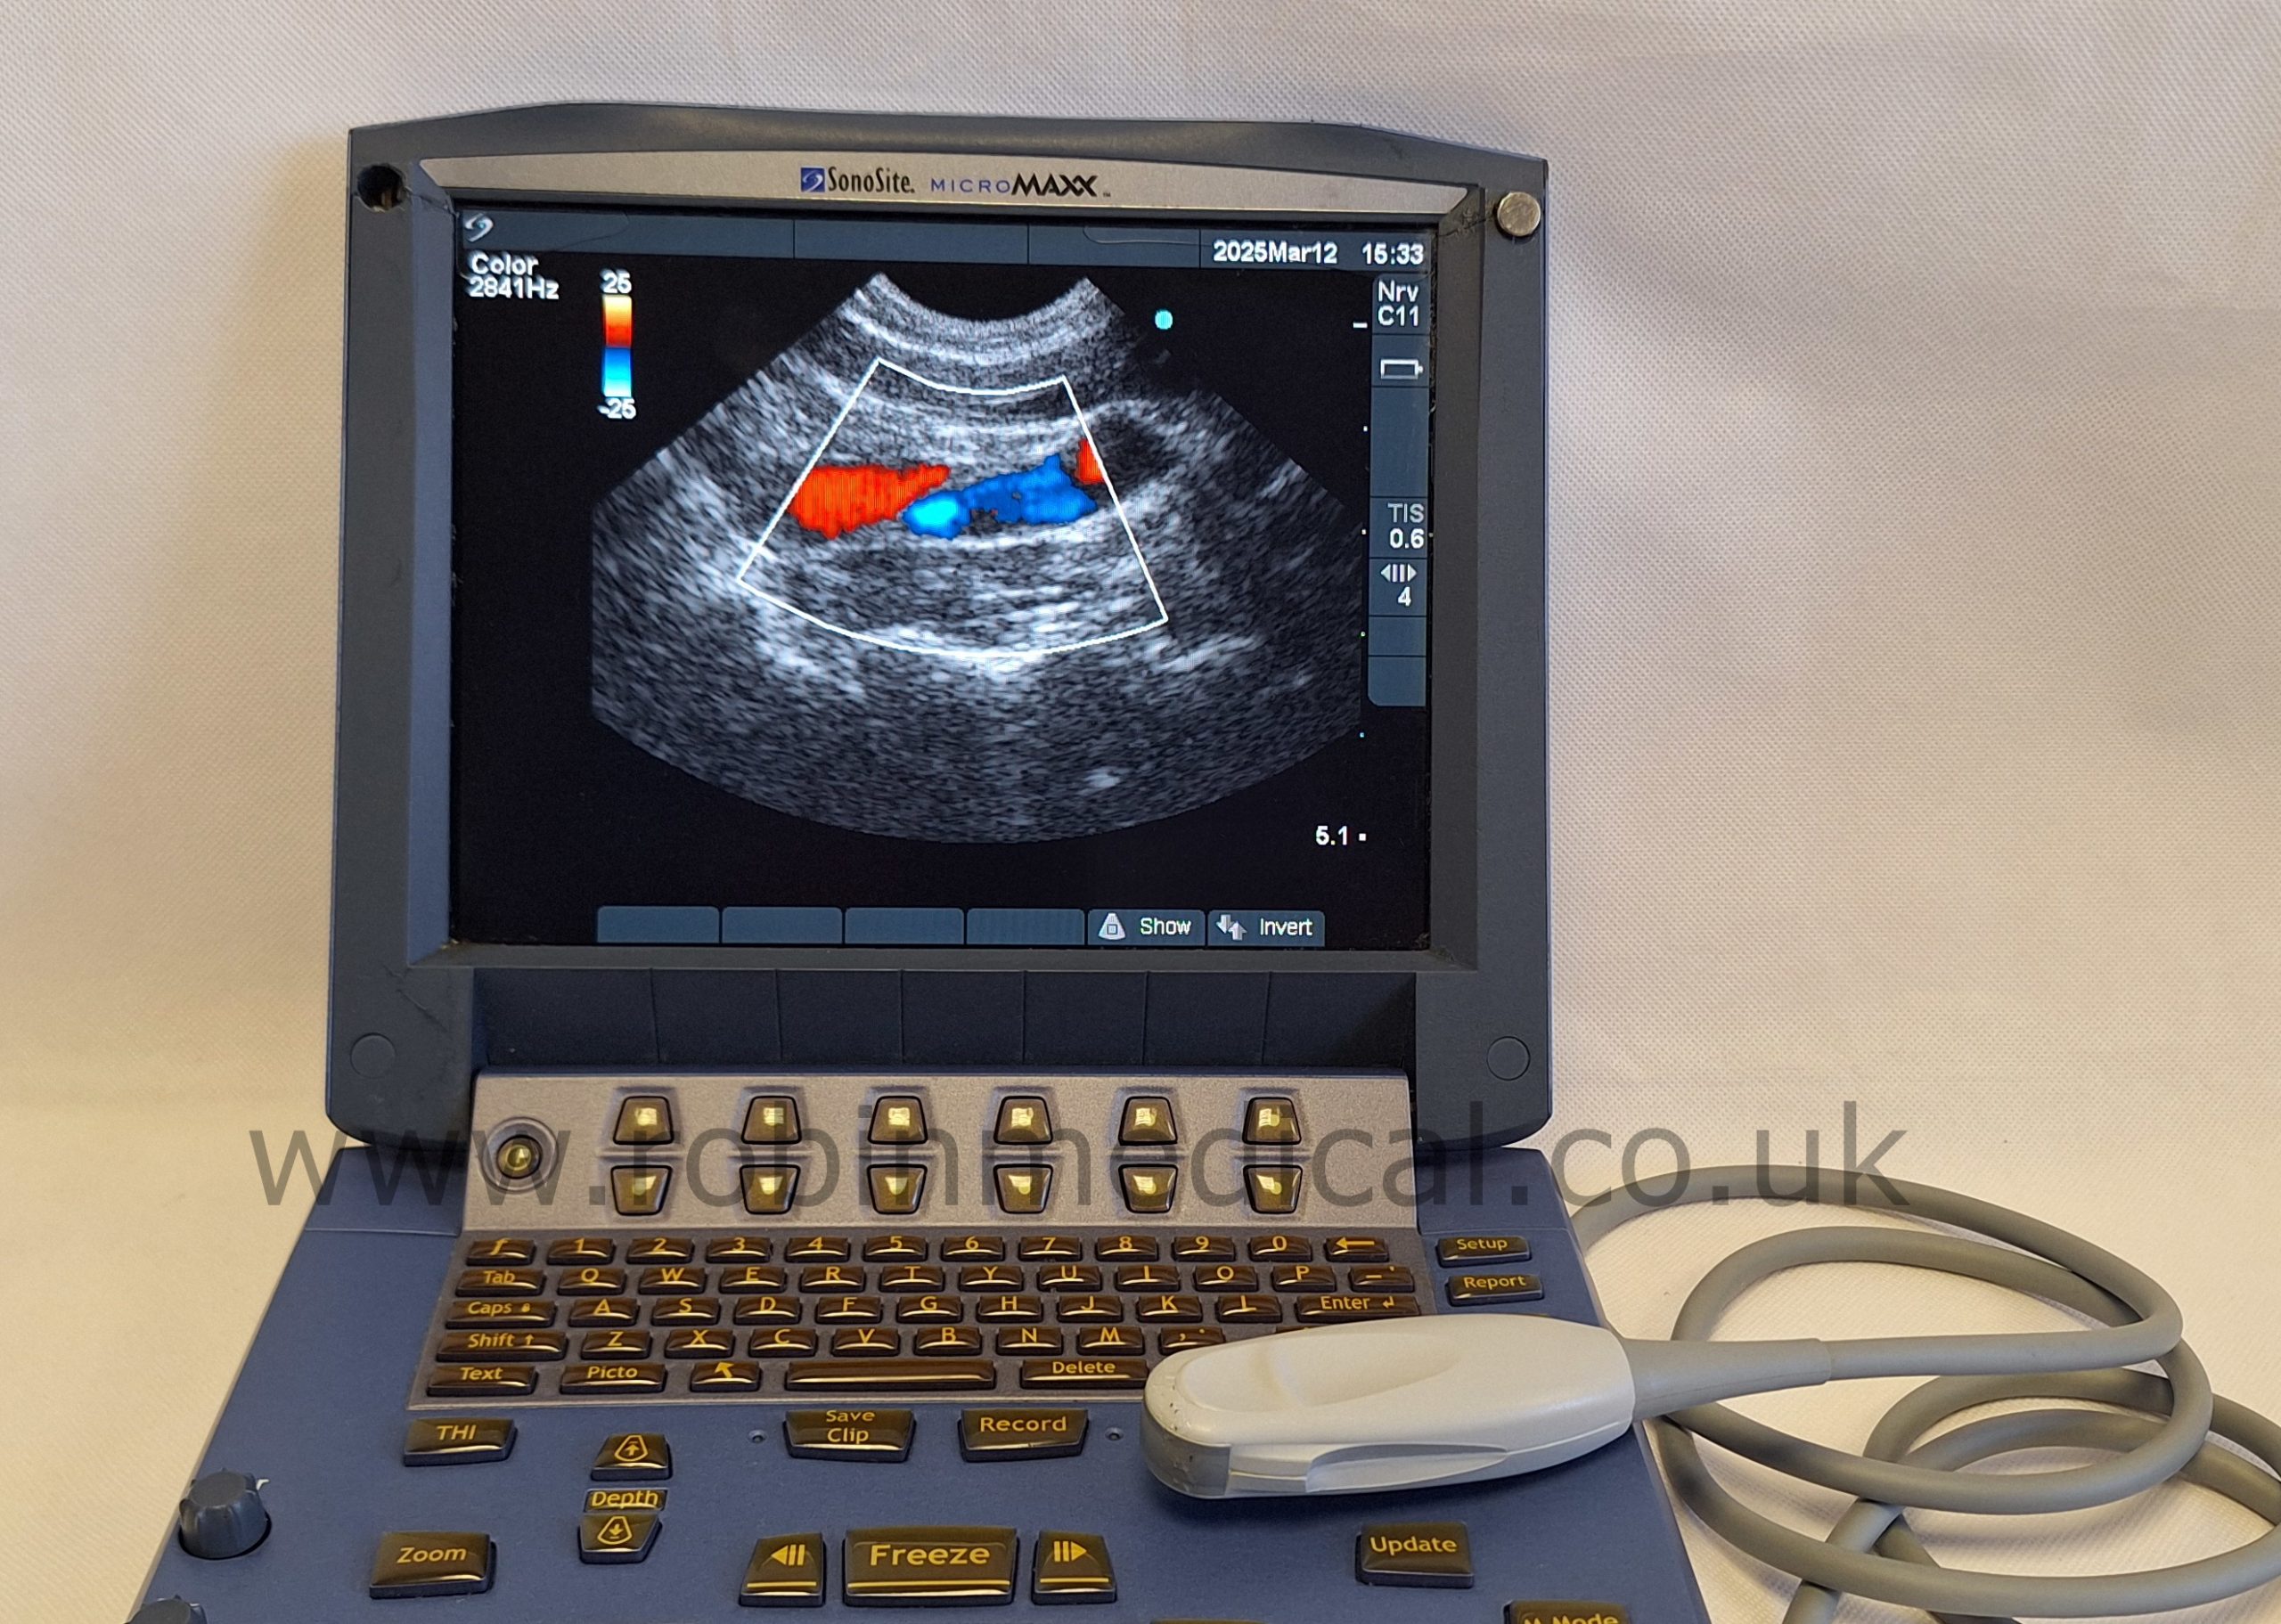

The Sonosite C11e P07161-16 is a high-performance curved-array transducer designed for the Sonosite MicroMaxx ultrasound system. With a frequency range of 8–5 MHz, it delivers exceptional imaging clarity for abdominal, pediatric, and vascular applications. Its compact 11 mm footprint makes it ideal for scanning in narrow or confined anatomical regions, while maintaining superb detail resolution. This probe offers versatility and portability in fast-paced clinical environments.

| Application | Abdominal, Pediatric, Vascular |

| Imaging Modes | 2D, M-Mode, Color Doppler |

The probe functions as intended and the condition is exactly as shown in images.